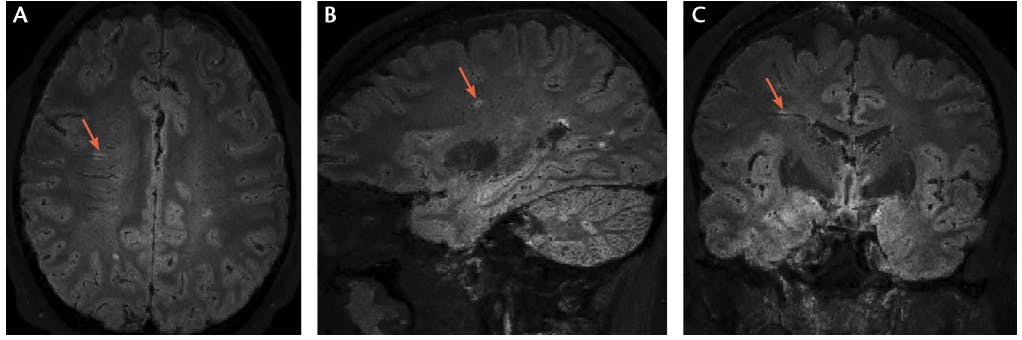

<p>Figure. The central vein sign on fluid‑attenuating inversion recovery* (FLAIR*) MRI.</p>

Figure. The central vein sign on fluid‑attenuating inversion recovery* (FLAIR*) MRI.

Many conditions mimic multiple sclerosis (MS) both clinically and radiologically. Despite validated diagnostic criteria,1 accurate diagnosis can be challenging. People without MS are misdiagnosed as having MS, often due to misattribution of MRI white matter lesions to MS. A novel imaging biomarker, the central vein sign (CVS), shows promise as a tool to distinguish demyelinating white matter abnormalities on MRI from lesions caused by other etiologies (eg, ischemia and migraine). Findings from pathologic specimens confirm that demyelinating lesions form around a postcapillary venule. Using susceptibility weighted MRI and standard fluid-attenuated inversion recovery (FLAIR) imaging, it is possible to determine if there is a CVS within an individual lesion (Figure). If validated, such a tool could significantly improve the accuracy of clinical diagnosis, allowing for more appropriate management of MS. Studies are underway to determine the best methods to capture and analyze this MRI finding.

The first report of a central vessel in MS lesions came from manuscripts prepared between 1829 and 1842 on the histology of MS plaques by anatomist Jean Cruveilhier.5 It was not until 150 years later, in 2008, that the first in vivo demonstration of these vessels was available with high-field MRI.6 The North American Imaging in Multiple Sclerosis (NAIMS) Cooperative provided a standardized definition for the CVS in their 2016 consensus statement (Table).7 The statement defined the CVS as a thin hypointense line or small dot positioned centrally in a lesion larger than 3 mm. The CVS is best visualized on susceptibility-weighted images coregistered to T2-images (eg, the FLAIR* technique) (Figure).